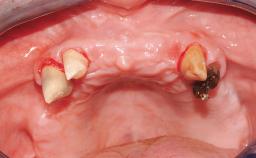

A 35-year-old Caucasian female presenting with advanced periodontal disease involving both the maxillary and the mandibular dentition was referred for evaluation. The patient, a non-smoker in good general health, requested treatment for recurrent periodontal abscesses, tooth mobility, and discomfort during chewing, as well as restoration of her missing teeth with a fixed prosthesis to improve mastication and esthetics. All residual maxillary teeth exhibited plaque deposits, deep pockets, bleeding on probing, and class III mobility and were evaluated as hopeless. All residual mandibular teeth except tooth 37 could be maintained after periodontal therapy.